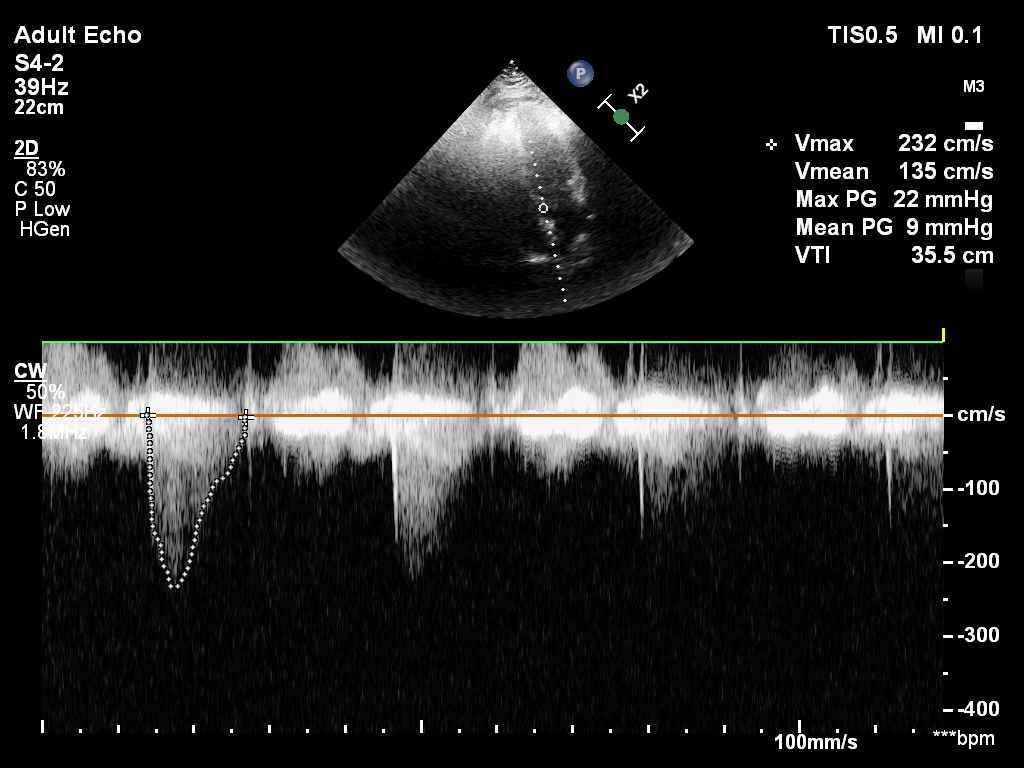

Przypadek 1.A

Przypadek 1.B

Przypadek 1.C